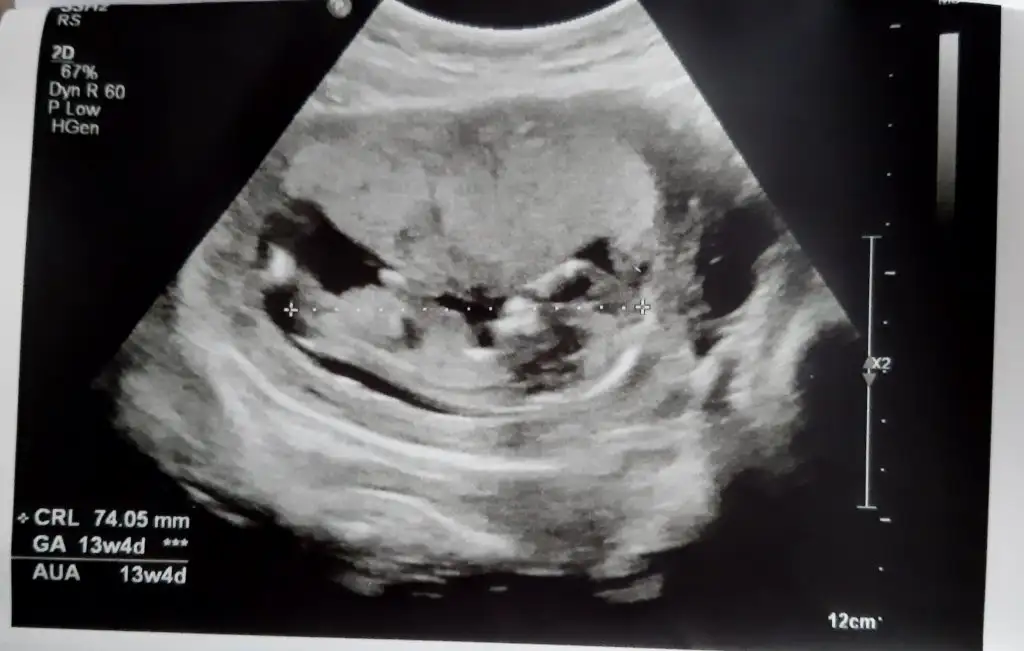

Kiz gibi sanki emin olamadımEki Görüntüle 2977845 İkra Meyra bizede bakabilir misin 12+4

Erkek gibi sanki12+1 fikri olan var mı?

Erkek gibi nubu dik görünüyor12 haftalik usg yorum yaparmisiniz rica etsem